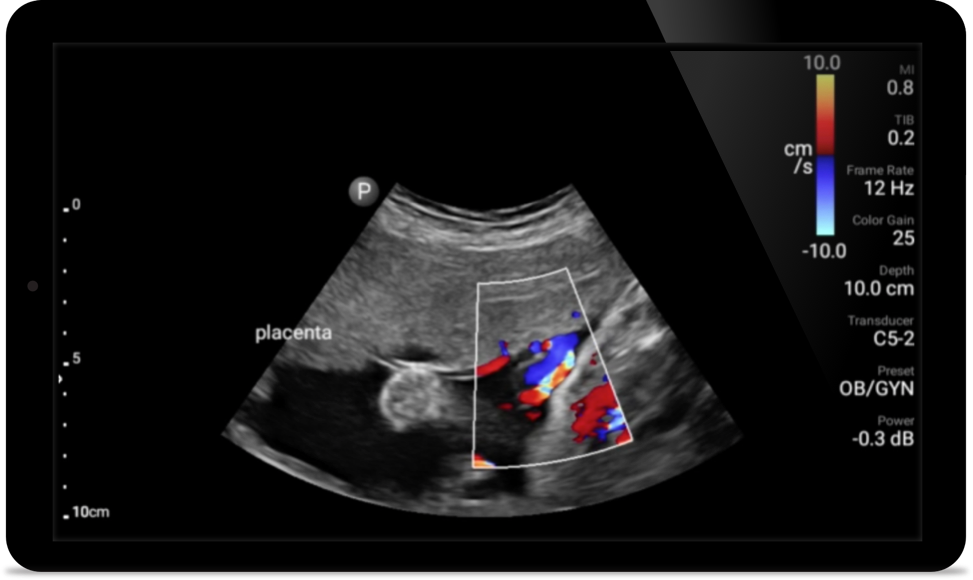

Second case image

Breathe easier with

Lumify

Lumify can help assess patients faster and improve

accuracy when diagnosing common causes of

dyspnea and other lung conditions.